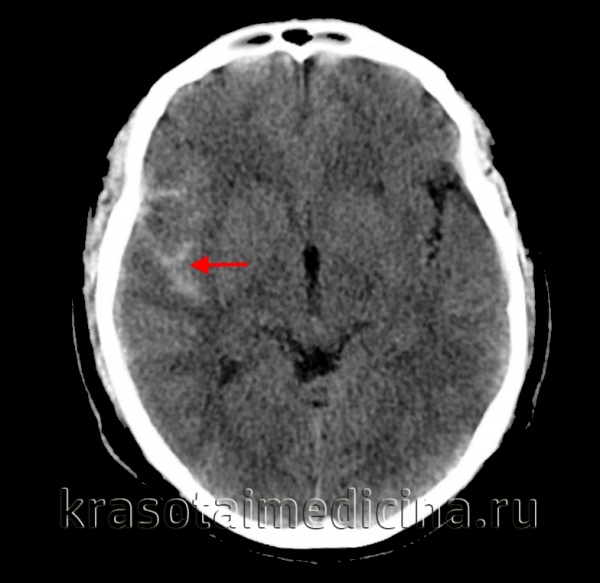

• Бесконтрастная КТ:

о Высокая плотность в субарахноидальном пространстве/цистернах

о Гиперденсная кровь в межножковой цистерне может быть единственным признаком слабовыраженного САК

о Признаки идентичны аневризмальному САК за исключением локализации:

- В области ушибов, субдуральной гематомы

- Борозды конвекситальной поверхности > базальные цистерны

(а) КТ, аксиальный срез: в бороздах, левой сильвиевой щели, обводной цистерне, а также в межполушарной борозде определяется гиперденсное субарахноидальное кровоизлияние.

(б) Бесконтрастная КТ, аксиальный срез: небольшое скопление гиперденсной жидкости вдоль левой средней лобной борозды, представляющей собой травматическое субарахноидальное кровоизлияние.